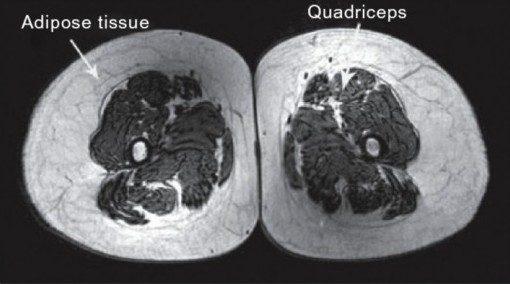

This is from a 70 year old Triathlete:

I Think he has got more muscle mass than the 40 year old.

No offence to the Triathletes but it would be interesting to compare this with some old Powerlifters or Cross-fitters.